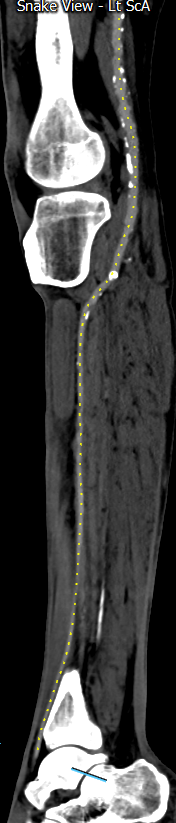

Urgent 3v PMEG rescue of symptomatic T1a EL in less than 3 hrs, including back-table time (less than anesthesia time). @FotehMazinMD @cfbechara @mattsmeds @GustavoOderich #VascTwitter #VascSurg #AortaEd @UIowa_Surgery